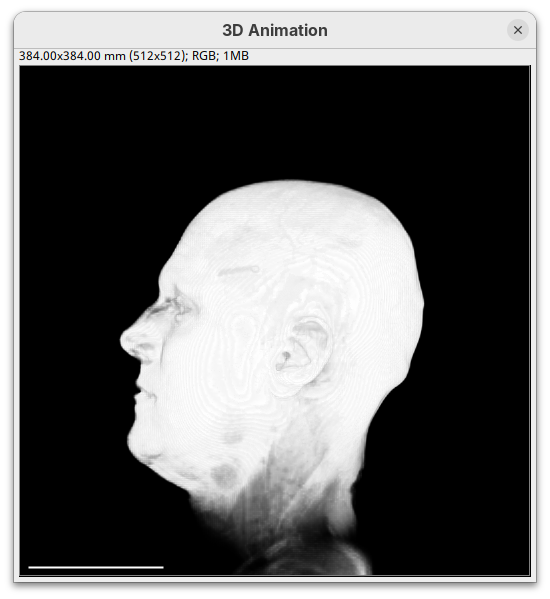

- Set the

minto0, for now. - Then, change the

maxto250.

The brightest parts of the rendering will become all white. It is so bright that we can no longer resolve details of the surface. We are losing information and also do not want that.